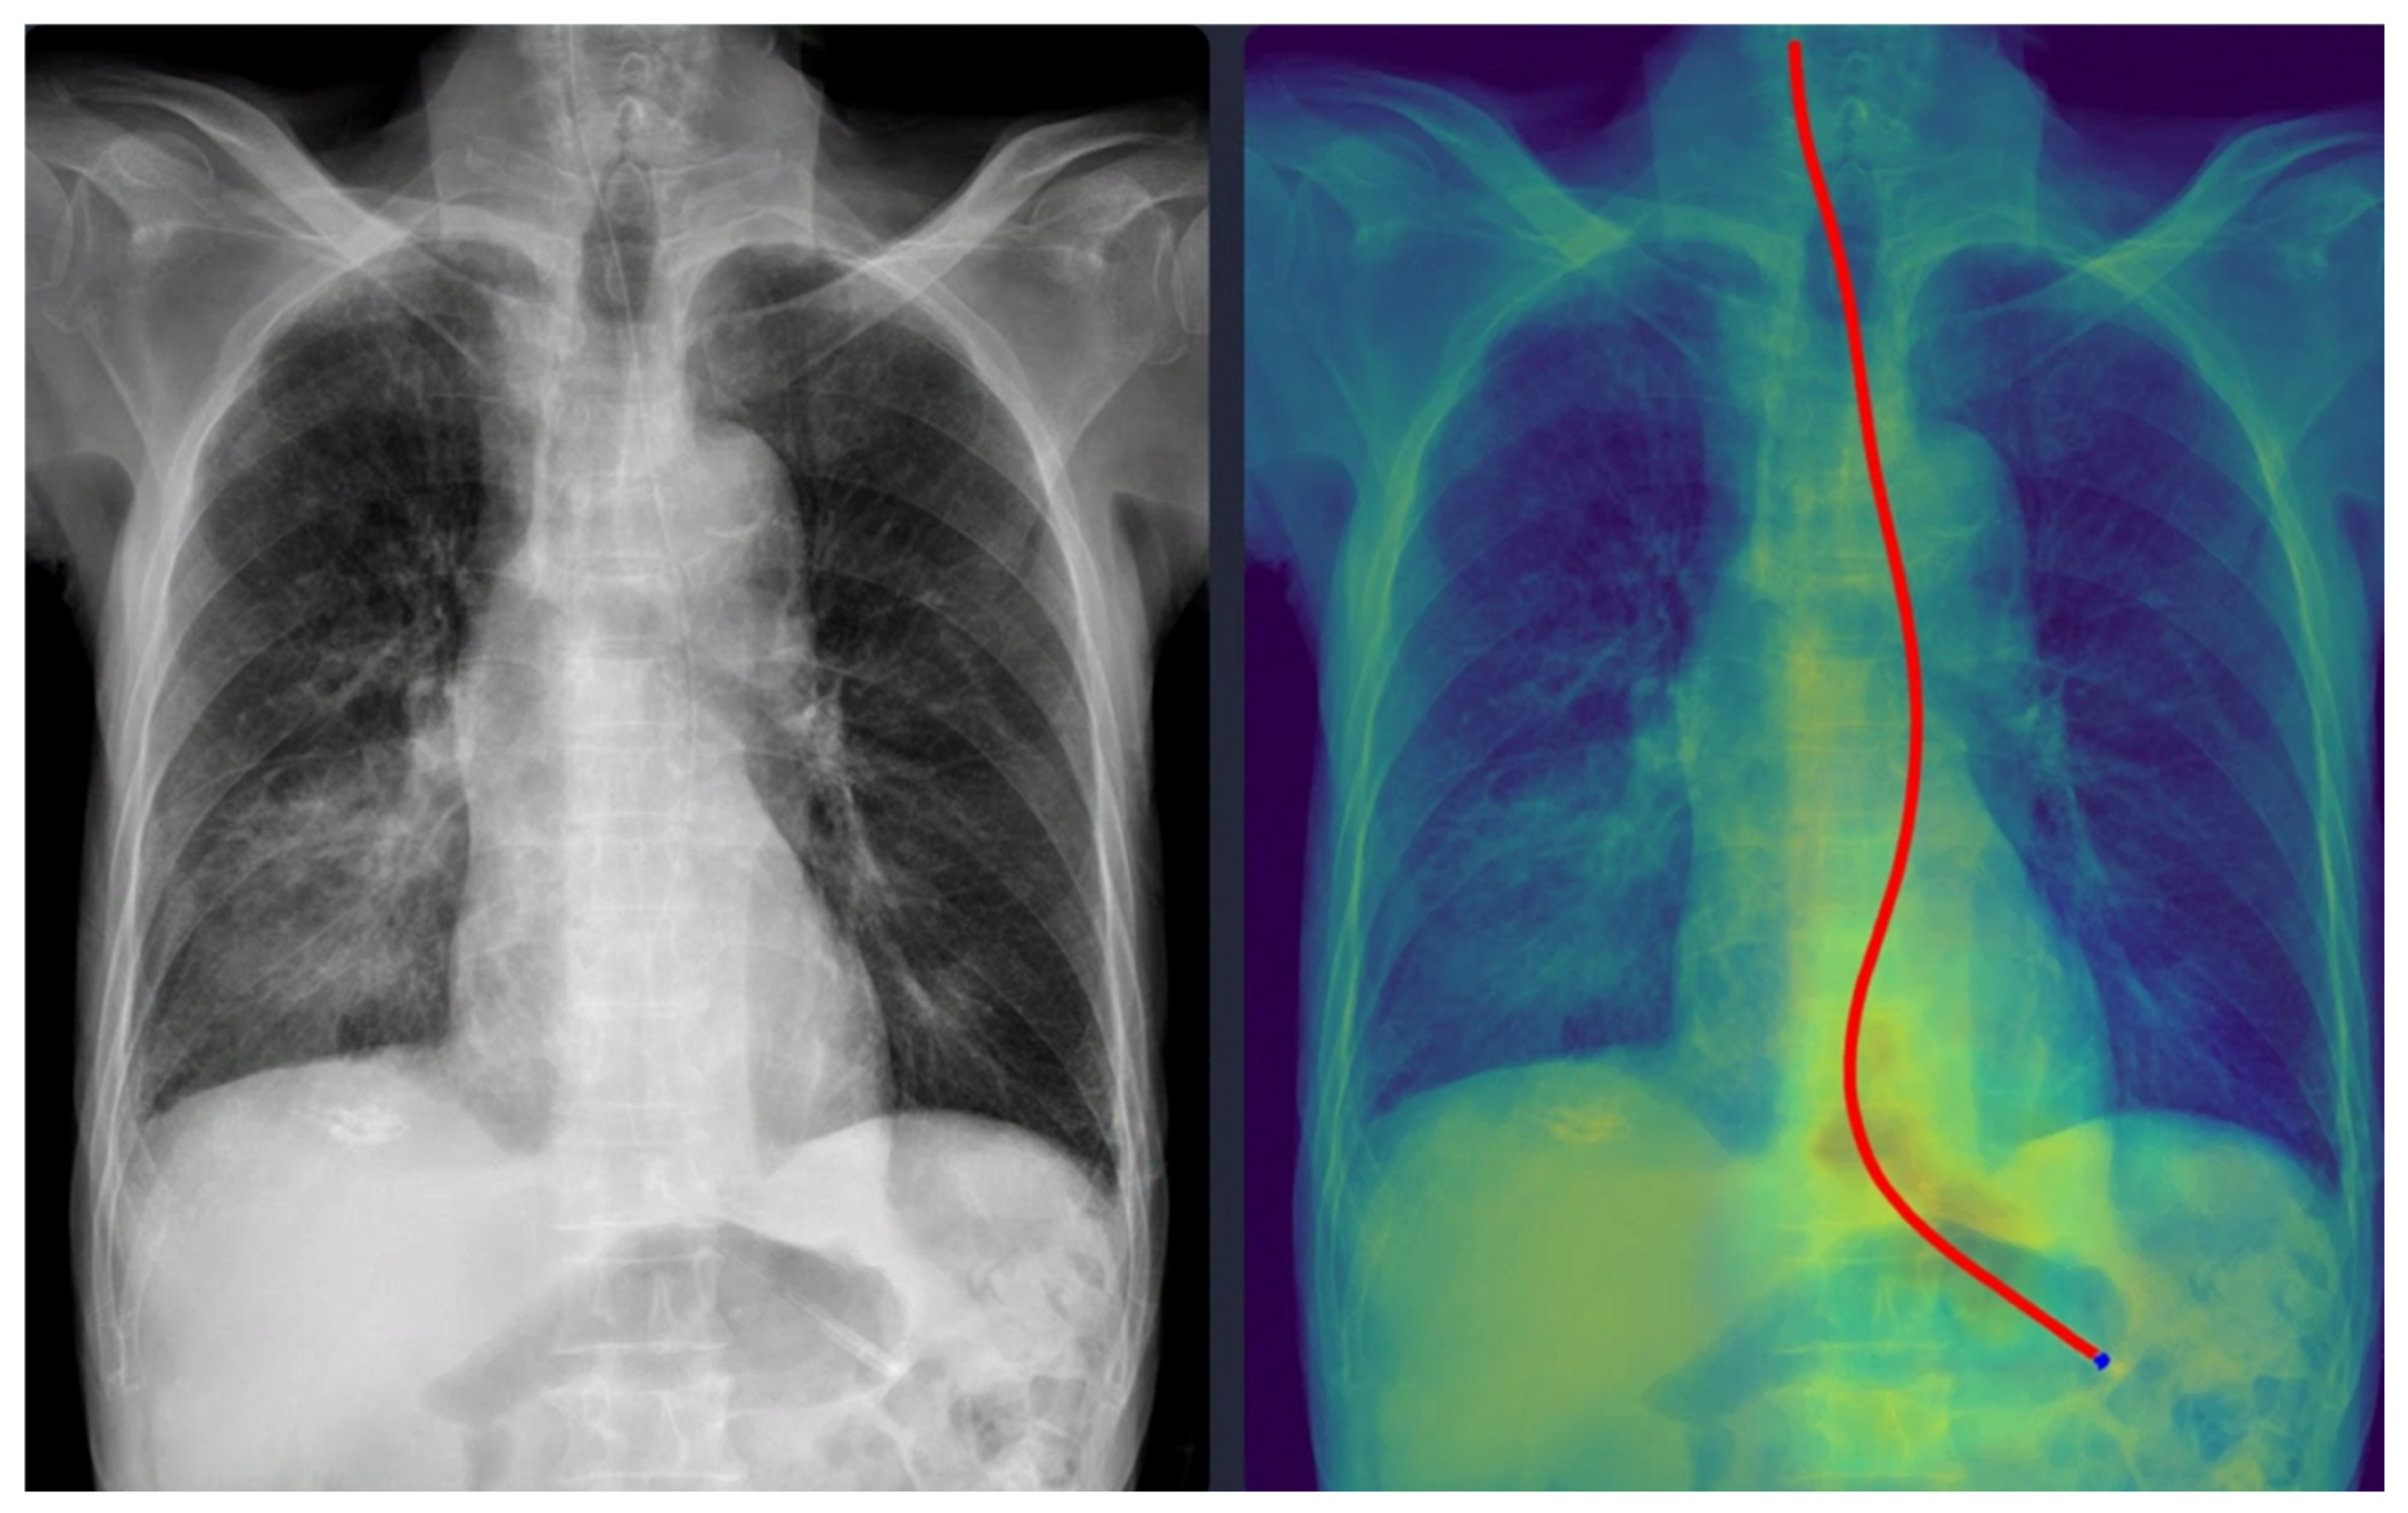

Representative examples of misclassified cases are shown in Figure 2 and Figure 3. The most critical failure involved an NG tube coiled at the indicated site in Figure 2, which suggested incomplete placement and a significant safety risk. The DL model misclassified this case as ‘complete’ based solely on the position of the tip projected below the gastroesophageal junction. Technically, this false-positive classification was highly likely due to the scarcity of such complex, coiled morphological features in the training dataset. While the segmentation module correctly identified the general tube structure, the dual-stage model failed to recognize this pronounced looping or coiling as an immediate risk factor, resulting in the classification module overriding the critical incomplete placement status. This finding identifies a crucial, previously unanticipated failure mode in the model’s design and carries substantial clinical significance, as initiating feeding through a coiled tube presents a high risk of aspiration pneumonia. Moving forward, efforts must focus on incorporating a greater diversity of these rare, yet clinically critical, coiled cases into the dataset to enhance the robustness of the tube segmentation process, thereby ensuring improved and safer clinical implementation. In Figure 3, the DL model failed to draw the entire trajectory of the NG tube and misclassified a complete case as incomplete. A representative example of a correctly classified case is shown in Figure 4. The tip of the NG tube is placed under the gastroesophageal junction and is safe to feed. Because most cases were correctly positioned (=95%), prevalence bias likely inflated the AC1 coefficient, and κ was lower despite near-identical classifications. Future studies should include more incomplete cases to obtain stable reliability estimates [12]. Prevalence-adjusted bias-adjusted kappa (PABAK) estimates were also evaluated with bootstrapping confidence intervals [13]. The results of the agreement among physicians and the DL model are shown in Table 4. Cohen’s κ showed the smallest estimate of 0.644 (95% confidence interval (CI): 0.366–0.922), which increased when using PABAK (0.911 (95% CI: 0.812–0.967)) and Gwet’s AC1 coefficient (0.956 (95% CI: 0.907–0.991)).

Five cases were misclassified as incomplete, although the NG tube was correctly positioned in the stomach (Figure 3). In these cases, the model’s predicted pathway stopped midway, likely because radiopaque structures such as the spine overlapped with the tube. This finding indicates that the model requires additional training with a more diverse dataset to improve its robustness against anatomical noise.

Figure 3. A misclassified complete nasogastric tube case identified as incomplete by the model. The arrow indicates the tip of the nasogastric tube. The red line represents the trajectory of the nasogastric tube as identified by the deep learning model.